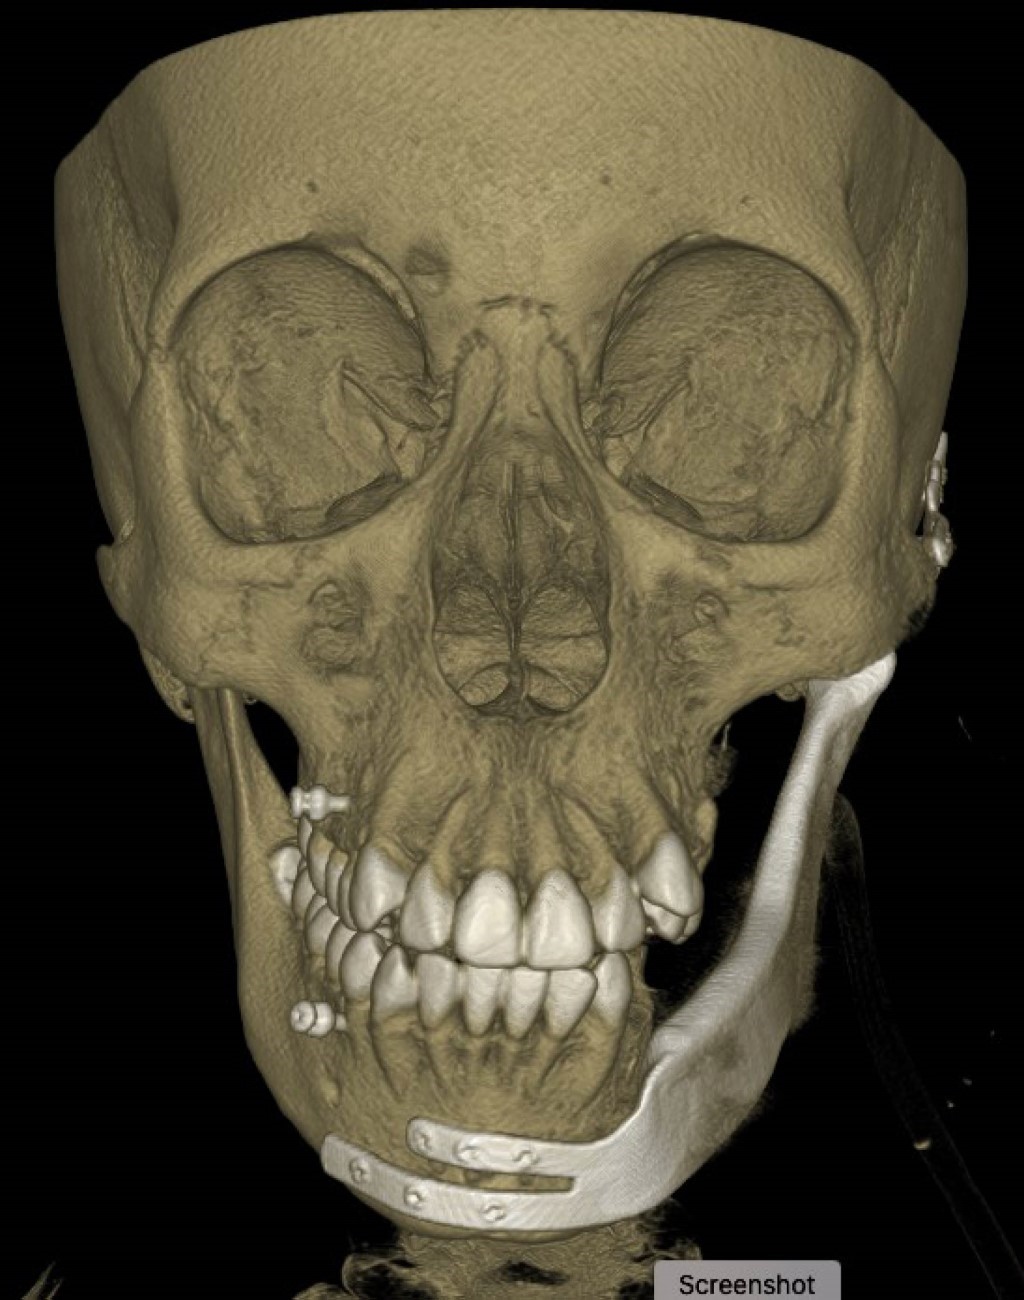

La planificación virtual permitió diseñar guías de corte para realizar la excisión de la lesión mediante mandibulectomía segmentaria dejando un margen de 1.5 cm (Figuras 7 y 8). Simultáneamente, se realizó la reconstrucción con prótesis personalizada, incluyendo la rama mandibular, cóndilo y cavidad glenoidea. La fijación se logró con tornillos del sistema 2.4 y 2.0.

Durante el procedimiento quirúrgico, posterior a la fijación de la parte anterior de la prótesis con el cuerpo mandibular remanente, se observó una discrepancia en el ajuste del cóndilo de la placa mandibular con la cavidad glenoidea, quedando éste en una posición posterior al centro de la cavidad metálica.

Después del procedimiento quirúrgico, se solicitó un estudio tomográfico control, observando el retiro completo de la lesión; sin embargo, el cóndilo de la prótesis mandibular se encontraba posterior a la cavidad glenoidea como se presentó durante el procedimiento quirúrgico (Figuras 10 y 11). A pesar de una discrepancia en la posición del cóndilo, la paciente presentó adecuada evolución funcional, sin recurrencia a ocho meses del procedimiento presentando movimientos de apertura y cierre mandibular adecuados y oclusión estable.

Figura 7

Figura 8

Figura 9

Figura 10

Figura 11